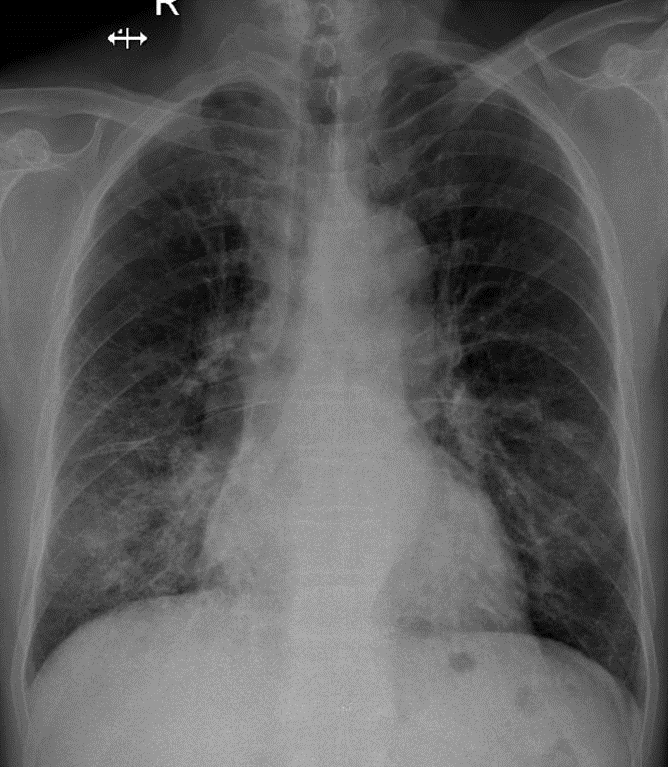

1-Thâm nhiễm phế nang và mô kè rải rác thùy dưới hai phổi => Viêm phổi